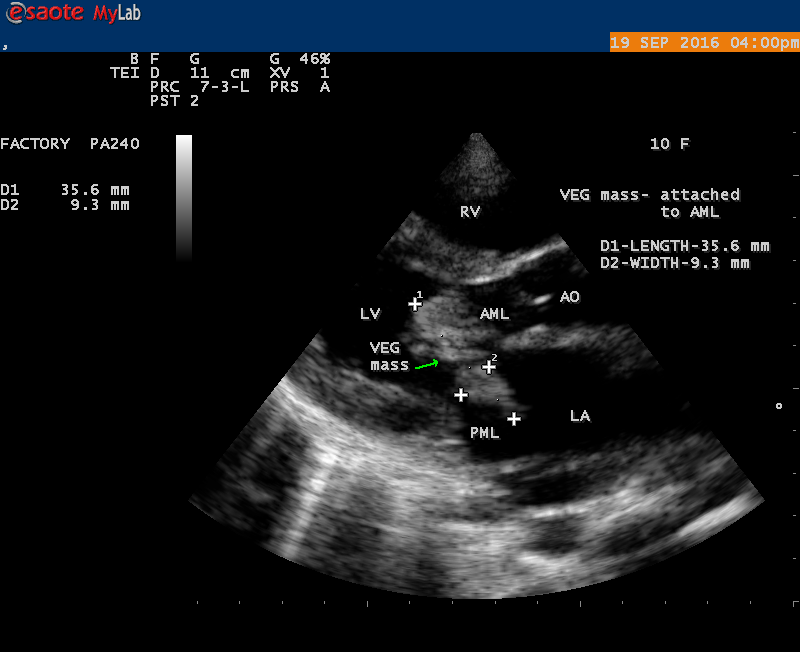

The most common and direct evidence of infective endocarditis is the vegetation and it begins as a microscopic focus of infection and gradually grows into a conspicuous mass. It is typically an irregularly shaped, highly mobile, echogenic mass attached to the free edge of a valve leaflet ( most commonly at the coaptation line) and tends to develop on the ‘upstream’ side of the valve leaflets ( ie, the ventricular side of aortic valve and the atrial side of mitral and tricuspid valves. They may be seesile or pedunculated, but usually has an oscillating or fluttering motion, a typical feature of most vegetations. Vegetation move with the leaflet in a more chaotic (‘oscillating’) manner and it may prolapse through the valve into the LV (left ventricle) as it opens as shown in Figures 3, 4 and 16 and into LA (left atrium) as it closing (Figure 5 and 6) . The mass of vegetation is typically homogeneous with echogenicity similar to that of the myocardium. The infectious process often alter the valvular structure and function. Extensive involvement of the leaflet may result in chordal rupture, leading to severe regurgitation as shown in Figure 21 . Direct and typical signs of RMCT (ruptured mitral chordate tendineae) were chain-flail or whiplash-like changes and had an incidence of 86.7%, causing severe regurgitation and mitral chordal rupture is the leading cause of flail mitral leaflet[30]. A large vegetation may obstruct the valve orifice as shown in Figure 1 and 2 , sometimes termed as “obstructive-type bacterial endocarditis” and producing a functional valve stenosis ( Ping-Pong mitral stenosis [31]) similar to left atrial myxoma as shown in Figure 29.

The shape and size of vegetation are quite variable and mostly it is polypoid [32]. The typical vegetation is a ‘sessile’ or ‘ pedunculating’ valve – attached mass. A ‘sessile’ vegetation had to be completely attached to the valve as shown in Figures 34 and 35 in a 63- year old male, in which a large vegetation is attached to the atrial side of anterior mitral leaflet [33-Figure 13.3-A], producing severe mitral regurgitation as shown in Figure 36 and a mobile vegetation showed a pedunculating part prolapsing into the ventricle as shown in Figure 3 and 4 or atrium as shown in Figure 5 [33-Figure 13.1] in a 10-year old female child. A vegetation was considered as ‘definite’ when shaggy echoes in the M-mode study as shown in Figure 20 . and a corresponding mass without restricted valve motion in the two-dimensional echocardiogram were found as shown in Figure 16 and 30 [33-Figure 13.7]. The vegetation vary in size, often being just a few mm and sometimes reaching to 2-3 cm. A vegetation must be atleast 3 to 6 mm in size to be reliably seen. The mean size of vegetation was 0.6 mm (range 3 to 28) and vegetation > 10 mm in diameter was defined as ‘large’ and those ≤ 10 mm in diameter was defined as ‘small’ and ≥ 15 mm is ‘very large’. Vegetations resulting from fungal infections (candida, aspergillus) are usually much bigger than bacterial vegetations and can be so big to be mistaken for a cardiac tumor. The large vegetations are at increased risk for embolic complications [34], especially on the anterior leaflet of the mitral valve with mobility [35]. A vegetation size of 3.2 x 4.4 cm is called as ‘giant vegetation’ on the mitral valve with a fibrillary appearance of the mass [36- Figure 3] as shown in Figure 1 is an important predictor of embolic phenomena in patients with infective endocarditis causing severe mitral regurgitation as ‘Duck’ shaped jets (Figures 24 and 25 ), disorganized (Figure 21) and sometimes the regurigitant jet splits into two components as one into LA and the second one into LV simultaneously as a bileaflet jets (Figure 10 ) similar to bileaflet structure of AML with vegetation masses (Figure 9 ) . The size of the largest vegetation reported on the mitral valve in the literature in patients with bacterial endocarditis is 7x4 cm[37]. In a study of Nunes, et al[38], vegetation size >13 mm was the only independent predictor of mortality, but some studies [39],[40] did not had an increased embolic risk in patients with vegetation focused only on its presence and size and not on their location. Embolic complications may occur in infective endocarditis(20.6%)and were not more prevalent in the groups with large vegetations [41]. However, Wong, et al [42] found an increased need for surgery in patients with a large vegetation (>10 mm).

The size and shape of vegetation vary due to curling of vegetation. The size of vegetation in this child is 35.6 x 9.3 mm as in Figure 17 , 20 x 23.7 mm as in Figure 1 , 32.9 x 13.9 mm as in Figure 2 .

The shape of vegetation varies in this child as ‘popcorn’ like (Figures 1,3 and 4 ), rod-shaped (Figure ), basket shaped (Figure 7 )[33-Figure 13.3], ‘baby in hand’ appearance (Figure 18), ‘cucumber shaped (Figure 2 ) and a ‘bunch of plantain’appearance (Figure 33 ), ring shaped (Figure 19 }, bileaflet structure (Figure 9 )with bileaflet MR jet as shown in Figure 10 . and kissing forms (Figure 13 - parasternal long axis view, Figure 14 - apical four chamber view and Figure 15 - short axis view)